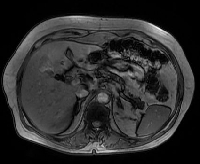

Πρόκειται για γυναίκα ασθενή 62 ετών η οποία, σε προ μηνός λαπαροσκοπική χολοκυστεκτομή (σε άλλο θεραπευτήριο), διαπιστώθηκε ότι έπασχε από χολαγγειοκαρκίνωμα της χοληδόχου κύστης. Περαιτέρω απεικονιστικός έλεγχος (MDCT, MRI) ανέδειξε υπολειμματική βλάβη στην κοίτη της χοληδόχου κύστης (εικόνα 1), καθώς και απουσία μεταστάσεων. Η ασθενής υποβλήθηκε σε λεμφαδενικό καθαρισμό της πυλαίας τριάδας (εικόνα 2) και ηπατεκτομή των τμημάτων 4b & 5 (εικόνα 3). Στο ιστολογικό παρασκεύασμα διαπιστώθηκε ότι η υπολειμματική βλάβη είχε μέγεθος 3.3 cm (εικόνα 4). Από τον ηπατοδωδεκαδακτυλικό σύνδεσμο απομονώθηκαν τέσσερεις λεμφαδένες (LNst 12a, 12b/p, 8 & 13), κανένας από τους οποίους δεν περιείχε νεοπλασματικά κύτταρα. Η ασθενής έλαβε εξιτήριο την 6η μετεγχειρητική ημέρα.